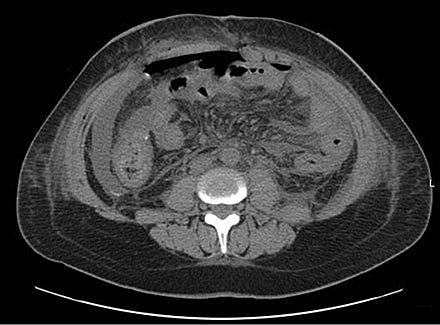

Intraperitoneal effusion med fri luft og ødem. Diffus peritonitis pga. anastomoslækage ved høj kolorektalanastomose [30]. Publiceres med tilladelse fra http://creativecommons.org/licenses/by/3.0/